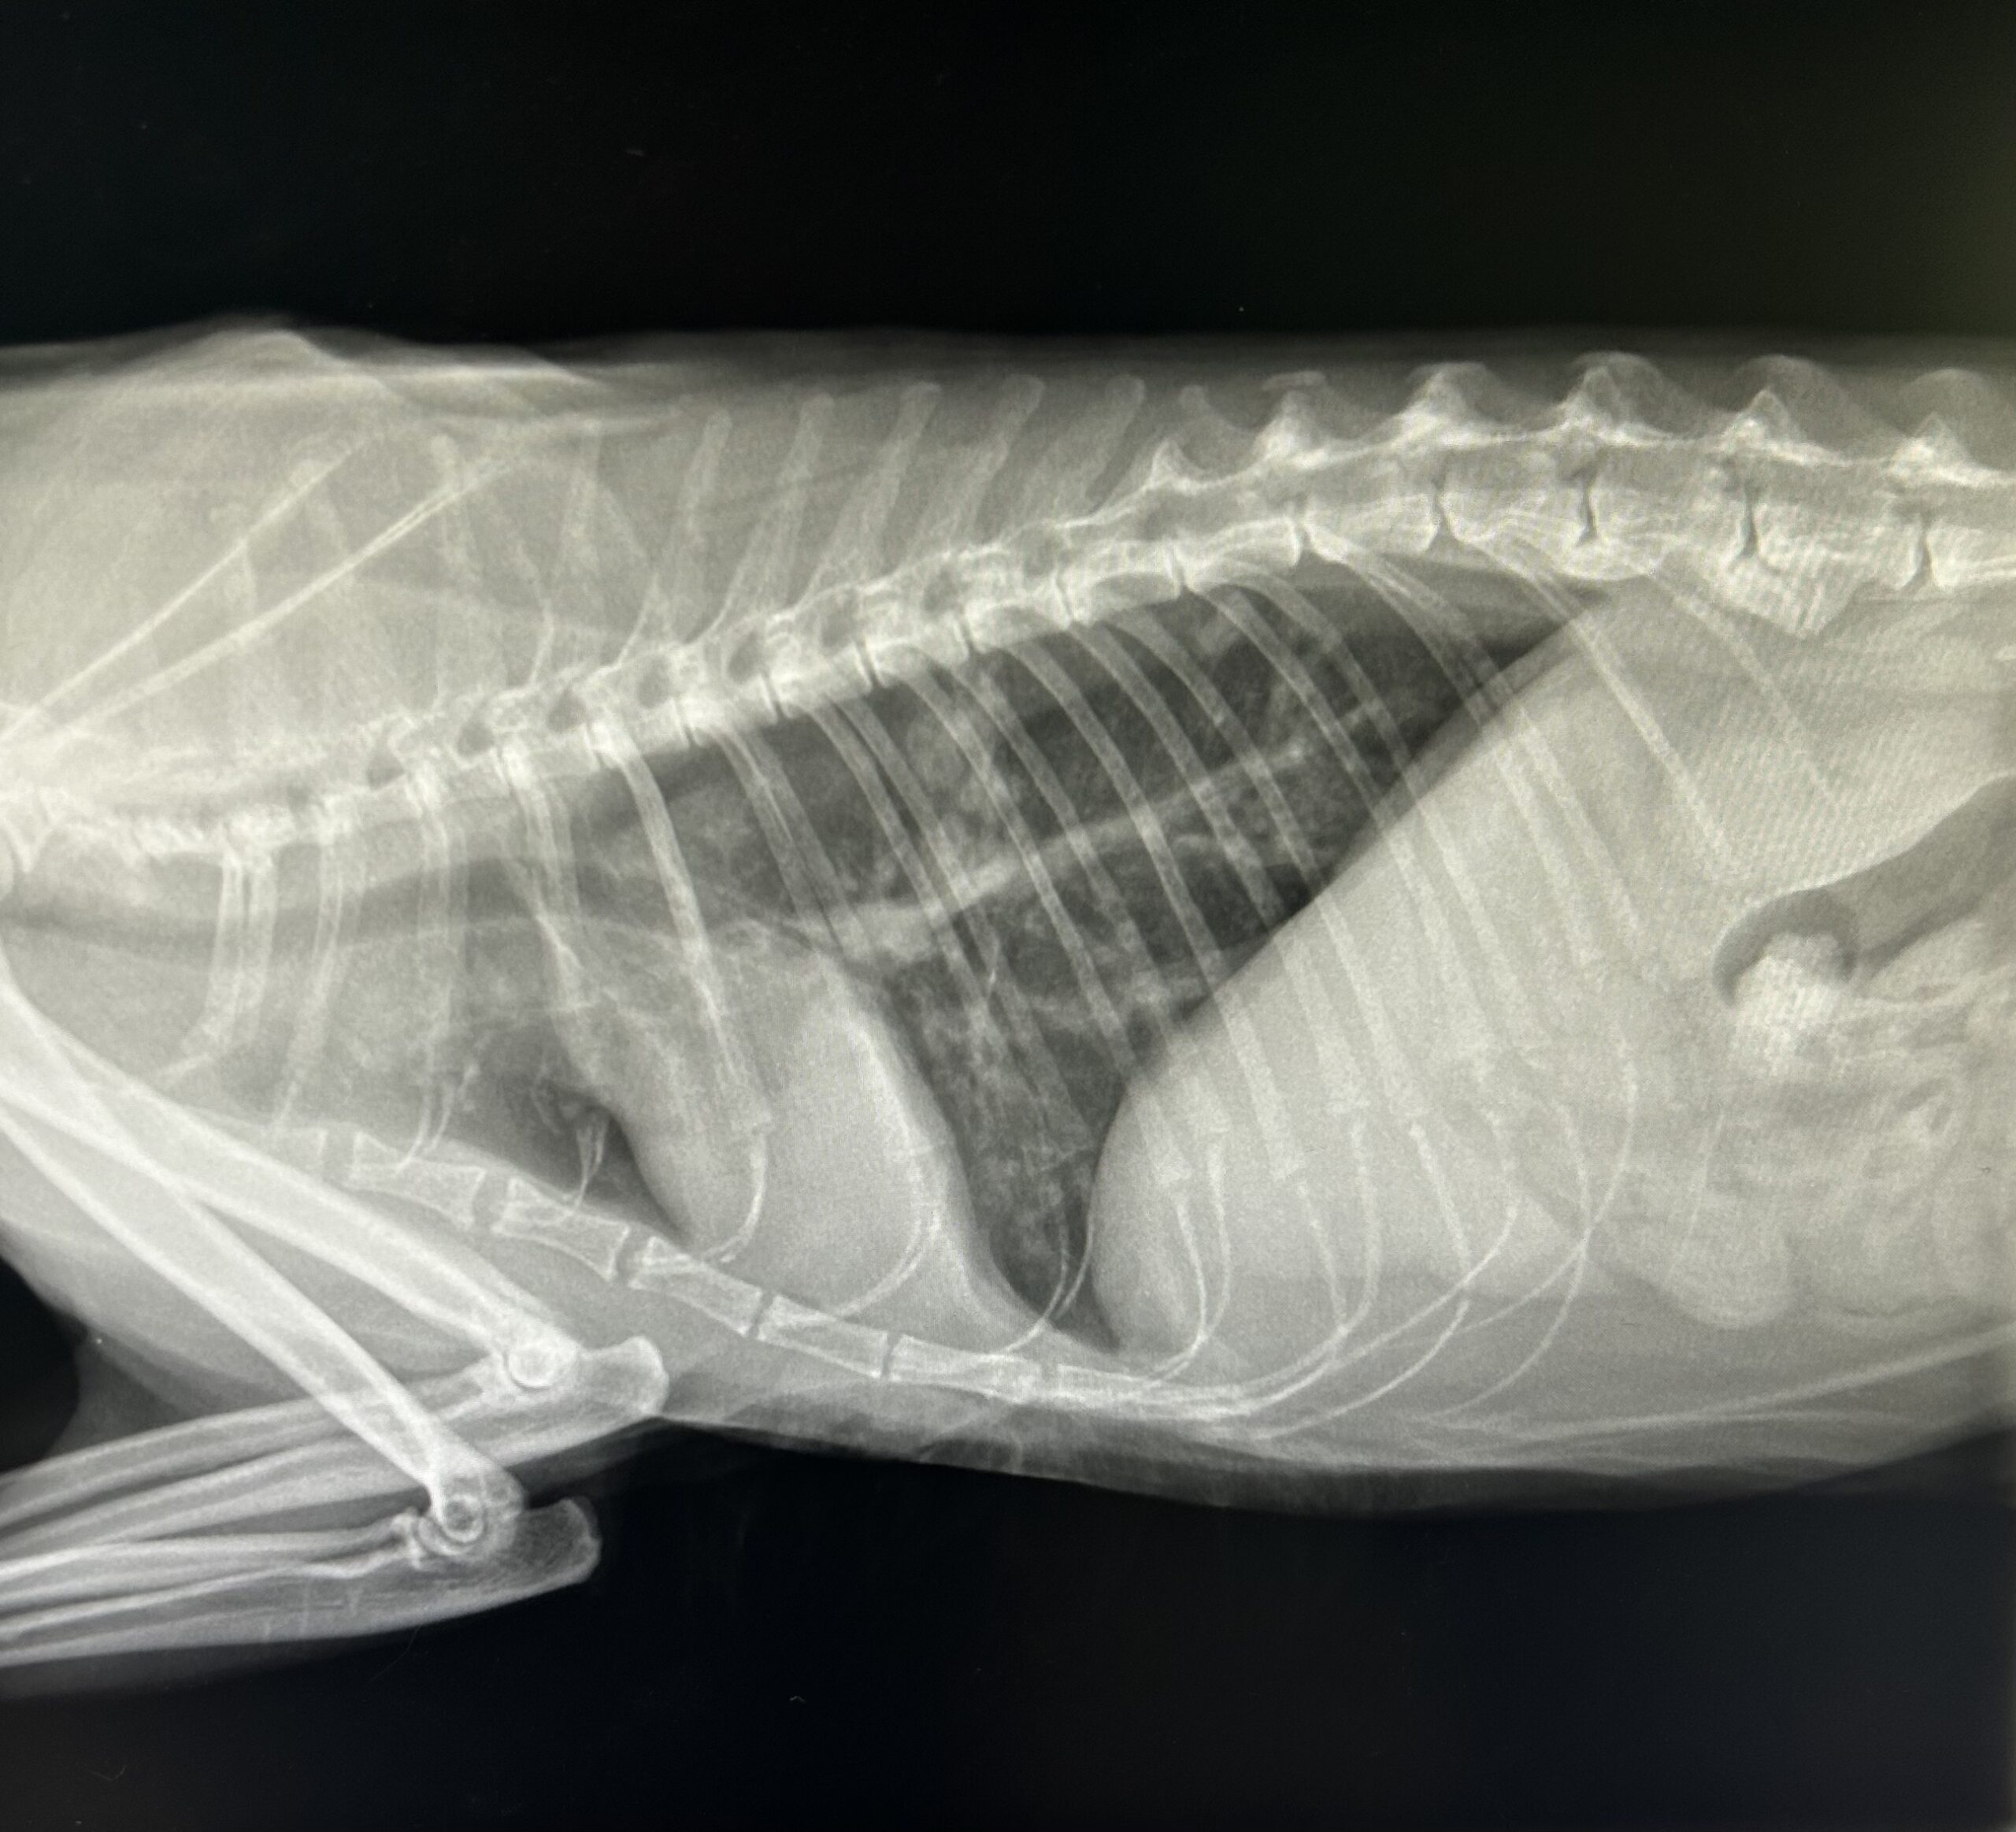

La radiographie est un examen complémentaire pratiqué le plus souvent sans tranquillisation et au résultat immédiat. Elle est particulièrement utilisée en traumatologie, pour

Nous réalisons également des radiographies officielles dans le cadre du dépistage des dysplasies (hanche et coude), conformément aux protocoles en vigueur.

Les clichés radiologiques de votre animal sont stockés dans son dossier médical informatisé.